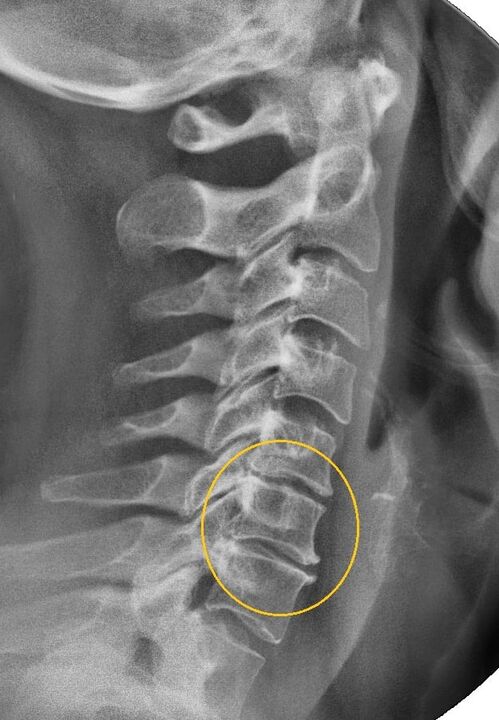

Najinformatívnejším diagnostickým postupom je rádiografia. Patológie 1. stupňa zodpovedajú 1. alebo 2. rádiologickému stupňu. Výsledné obrázky vizualizujú typické znaky ochorenia.

| Röntgenové štádiá cervikálnej osteochondrózy 1. stupňa | Charakteristické znaky |

|---|---|

| 1. fáza | Drobné zmeny v zakrivení chrbtice v krčnej oblasti, postihujúce jeden alebo viac segmentov |

| 2. fáza | Mierne zhrubnutie medzistavcových platničiek, deformácia výbežkov bez tela, napriamenie lordózy, drobné výrastky kostných štruktúr |